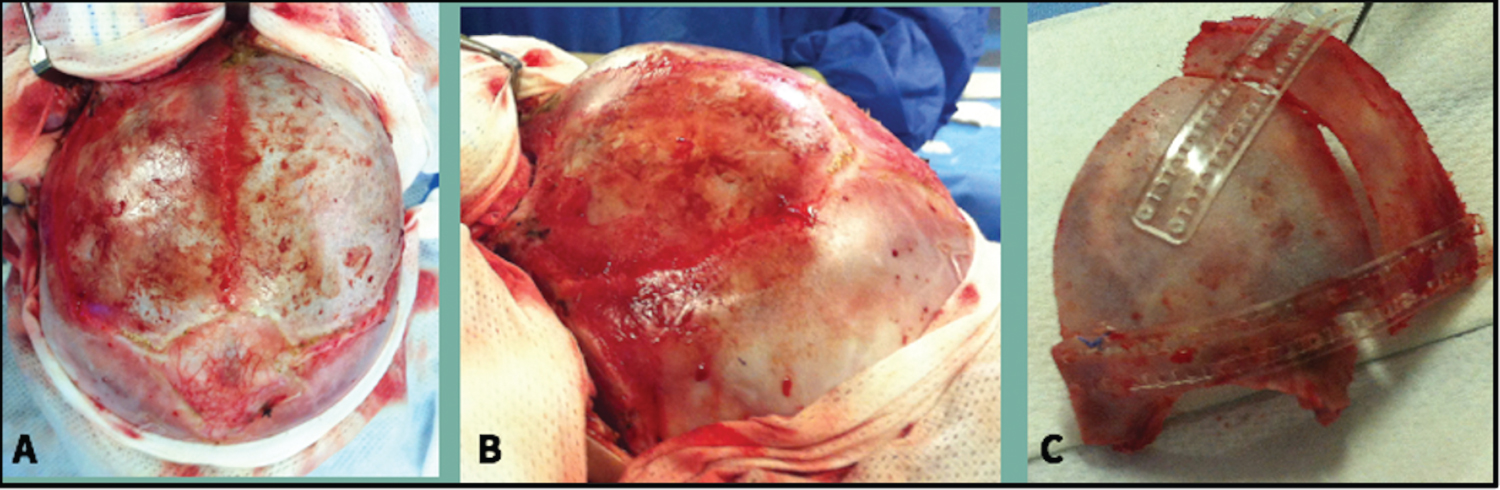

Surgical Technique

In our three patients, a left-sided advancement of a fronto-orbital bandeau was performed with frontal reshaping in "shell" variant [21] or with a Tessier bone bender as shown in Figure 5 and Figure 6. In frontosphenoidal craniosynostosis the orbital rim is displaced downward and backward compared to healthy side. So, the aim of surgical correction consists of advancement of the orbital edge and achievement of a elevation of the lateral canthus of the affected side together with a symmetric frontal bone flap on the synostotic side to create a normal-looking forehead. Bandeau reshaping and advancement in conjunction with the frontal bone were tailored to the magnitude of the craniofacial deformity in each individual patient, and unaffected side was used as a template for accurate surgical correction. The different bony segments were fixed with resorbable plates and screws. The surgery was well tolerated in all cases and the patients had an uneventful postoperative course.

Figure 5: Surgical technique. D) Detail of the osteosynthesis on the inner side of the bone flap; E) The compass shows the orbital advancement performed; F) The compass indicates the ascent of the orbit obtained. View Figure 5

Figure 6: A,B) Show the retrusion and downward displacement of the orbital rim associated with synostosis; C) Remodeling obtained after frontal advancement and elevation of the supraorbital rim. View Figure 6